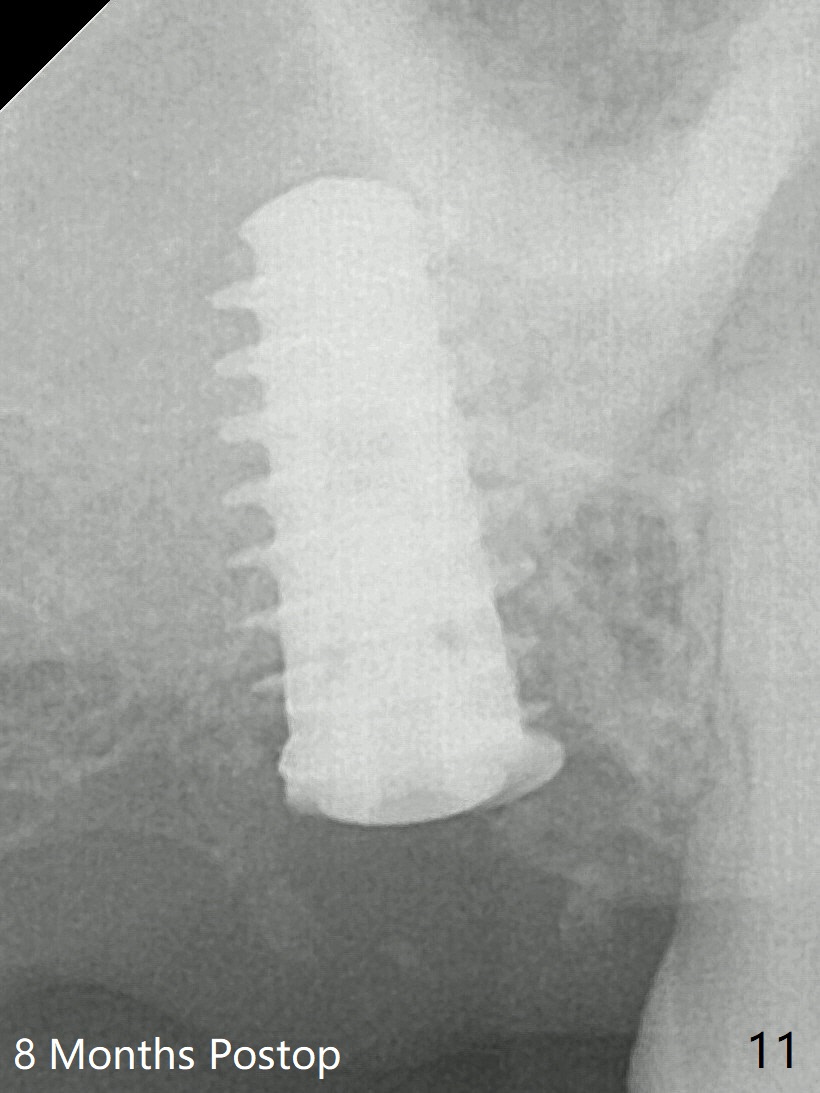

Five months post op, the healing abutment has mobility with light tenderness. The space between the bone and implant is larger than normal (Fig.10). The implant is stable with the healing screw 8 months postop (Fig.11). There is definitive sign of osteointegration 12 months postop (3 months post cementation, Fig.12). The final pair abutment is 5x4(4) mm. The patient is pleased to have the implant for 1 year 7.5 months post cementation (Fig.13).